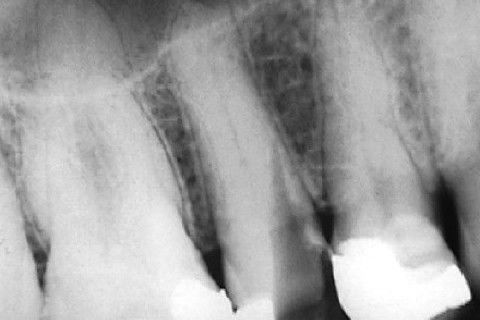

Calcificação Distrófica